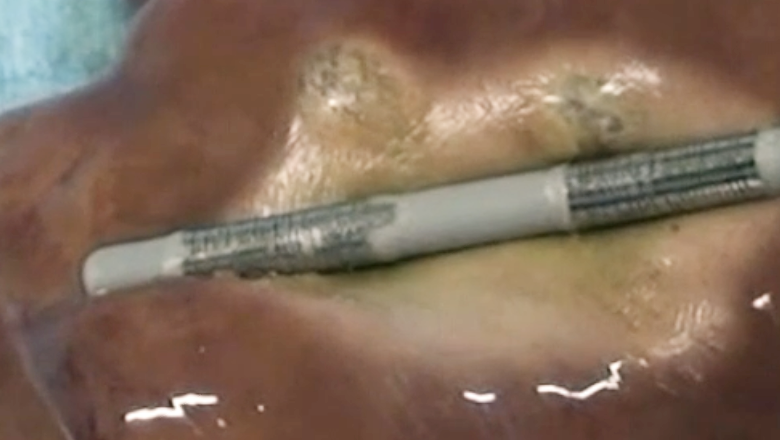

ERCP下腫瘍ラジオ波焼却術